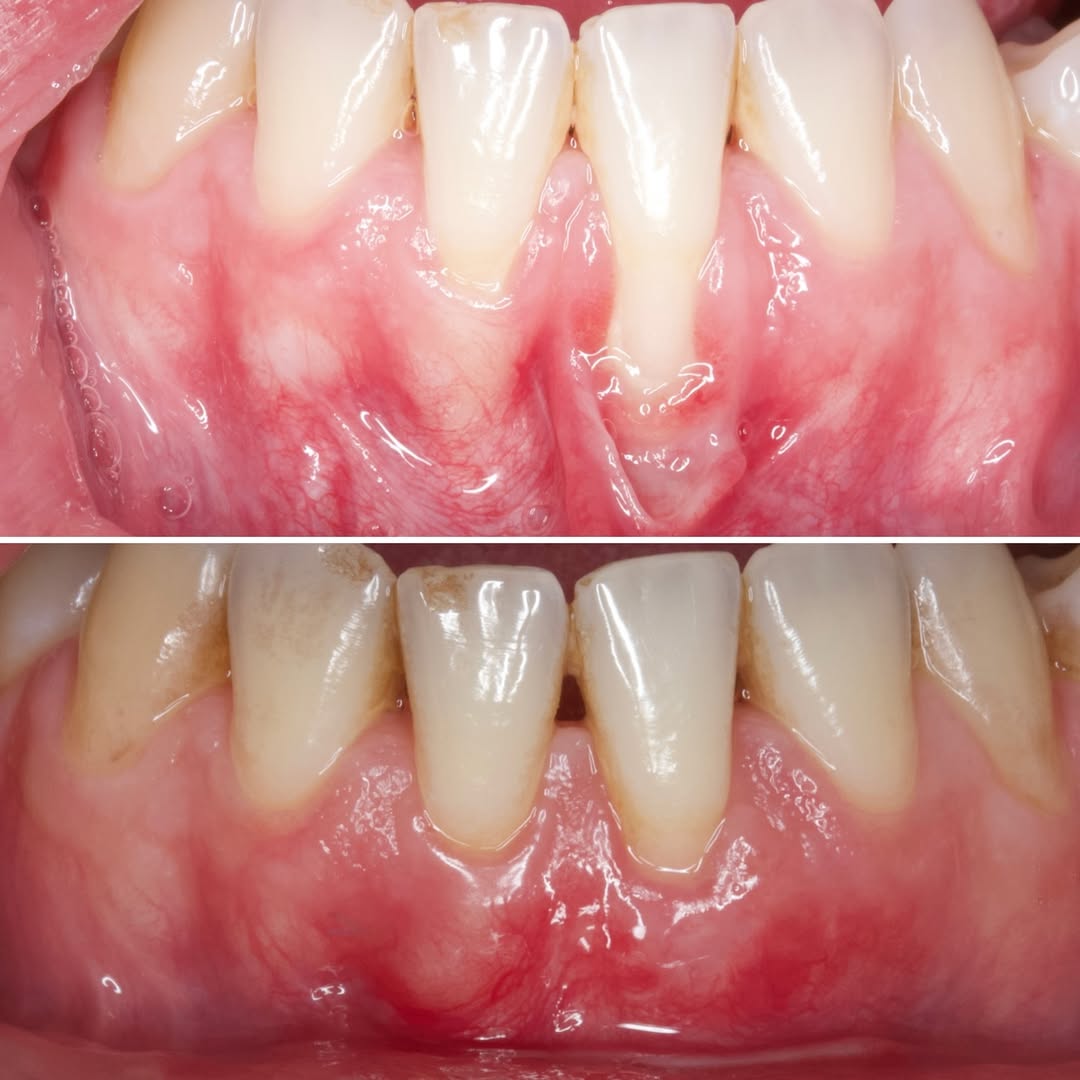

Durante una mañana, asistirás a una Cirugía Mucogingival de recubrimiento radicular de recesiones múltiples en IV y V sextante (36 a 43).

Gracias al uso del microscopio y a la proyección en tiempo real en pantalla, verás exactamente lo mismo que veo yo durante la cirugía, sin tener que estar

¿Te sientes seguro manejando recesiones múltiples o biotipos finos? Este curso está diseñado para transformar tu destreza quirúrgica en el manejo de tejidos blandos.

• Diagnóstico de Precisión: Clasificación de las recesiones y toma de decisiones basada en la

Aprende la planificación y técnica de la cirugía Mucogingival para el recubrimiento de recesiones y aumento de banda queratinizada en el sector anteroinferior

Una estancia clínica pensada para quienes quieran iniciarse o dar un paso más en el campo de la cirugía mucogingival. Durante esta experiencia tendrás la oportunidad de aprender en directo cómo se planifica y se lleva a cabo una cirugía mucogingival mediante técnica de Túnel.

La sesión